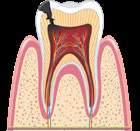

руйнуються під дією органічних кислот, які виділяються численними бактеріями ротової порожнини. Ці бактерії живляться залишками нашої їжі. Карієс виникає через недостатню

гігієну порожнини рота, переважання в раціоні м’якої їжі й вуглеводів. Розвиток карієсу

спричиняє нестача мінералів і вітамінів, які беруть участь у формуванні твердих тканин зубів: Кальцію, Флуору, Фосфору, вітаміну С та інших. До ушкодження емалі зубів також

призводить вживання гарячих, холодних чи

кислих напоїв. Руйнування зуба відбувається

внаслідок бактеріальної інфекції його тканин. X Правила профілактики